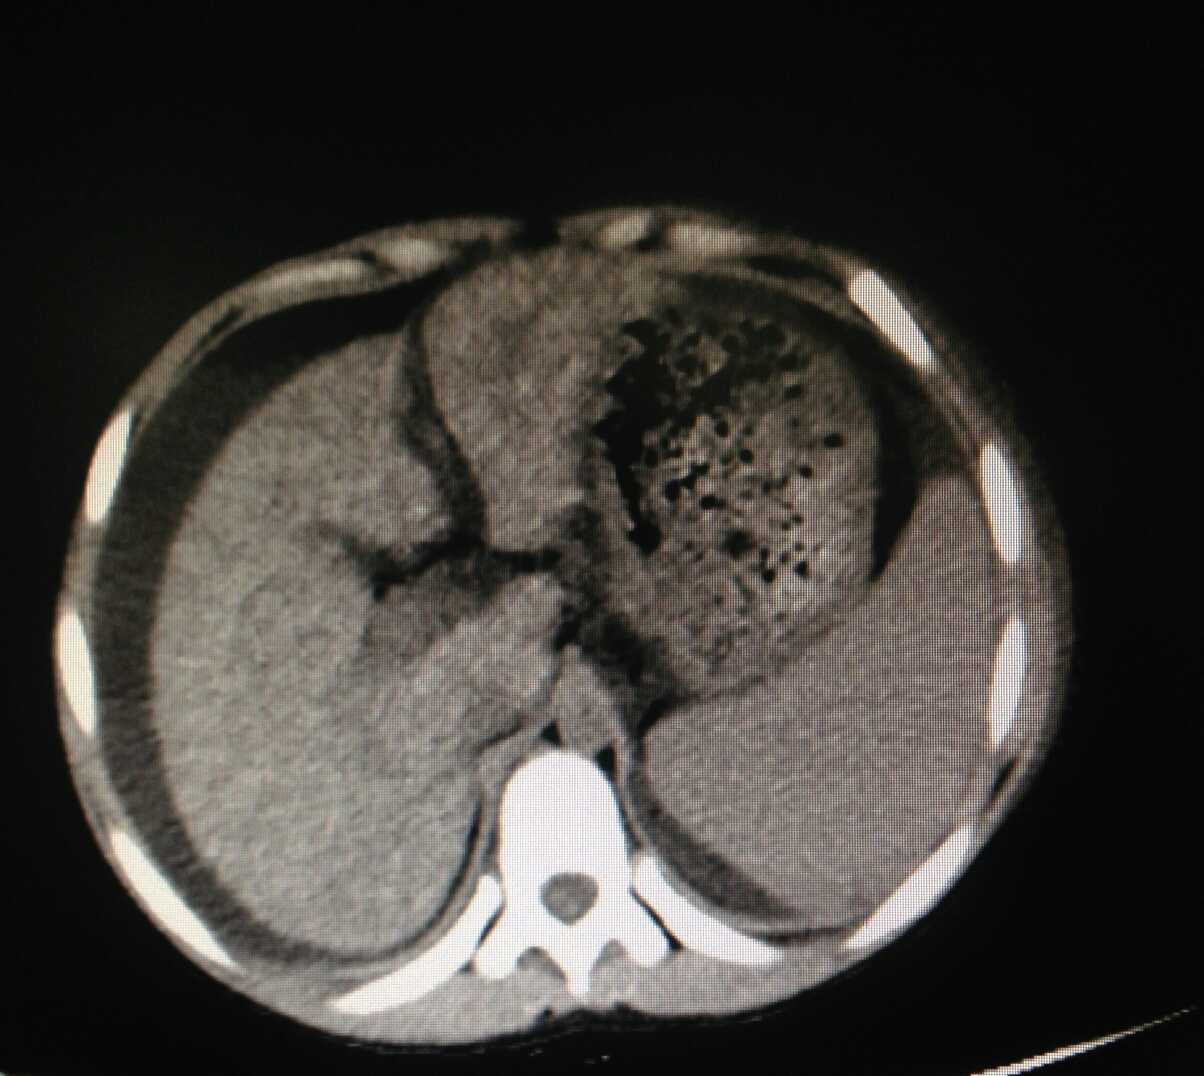

患儿,男,9岁,因“发现腹部膨隆1周”入院。患儿1周前出现腹部膨隆,无触痛、发热、咳嗽、乏力、食欲减退等不适,至当地医院就诊,查腹部超声提示肝光点密集增粗,脾中度肿大,腹腔大量积液。腹部CT提示肝硬化,脾大,腹水。肝炎病毒相关检查未见异常。肝功能:总胆红素66.4umol/l,直接胆红素46.1umol/l,间接胆红素20.3umol/l,白蛋白29.1g/l,谷丙转氨酶51U/L,谷氨酰转肽酶255U/L。甲胎蛋白:45.21IU/ml。体查:全身皮肤暗黄色,未见皮疹、皮下出血点,未见肝掌及蜘蛛痣,心肺听诊无明显异常,腹部膨隆,腹围69cm,无压痛、反跳痛,移动性浊音阳性。实验室检查:生化:ALT 45IU/L, AST 101IU/L。腹水常规:红细胞 140M/L,白细胞60M/L,腹水生化:葡萄糖6.7mmol/l,总蛋白8.3g/l,白蛋白0.1g/l,甲胎蛋白4.2ug/l。铜蓝蛋白<0.07ug/l。胸腹部CT:1、双肺炎症,2、肝硬化、脾大、腹腔大量积液。肝脏B超:肝硬化声像,胆囊壁增厚、粗糙、脾大,腹腔少量积液。头颅MRI未见明显异常。